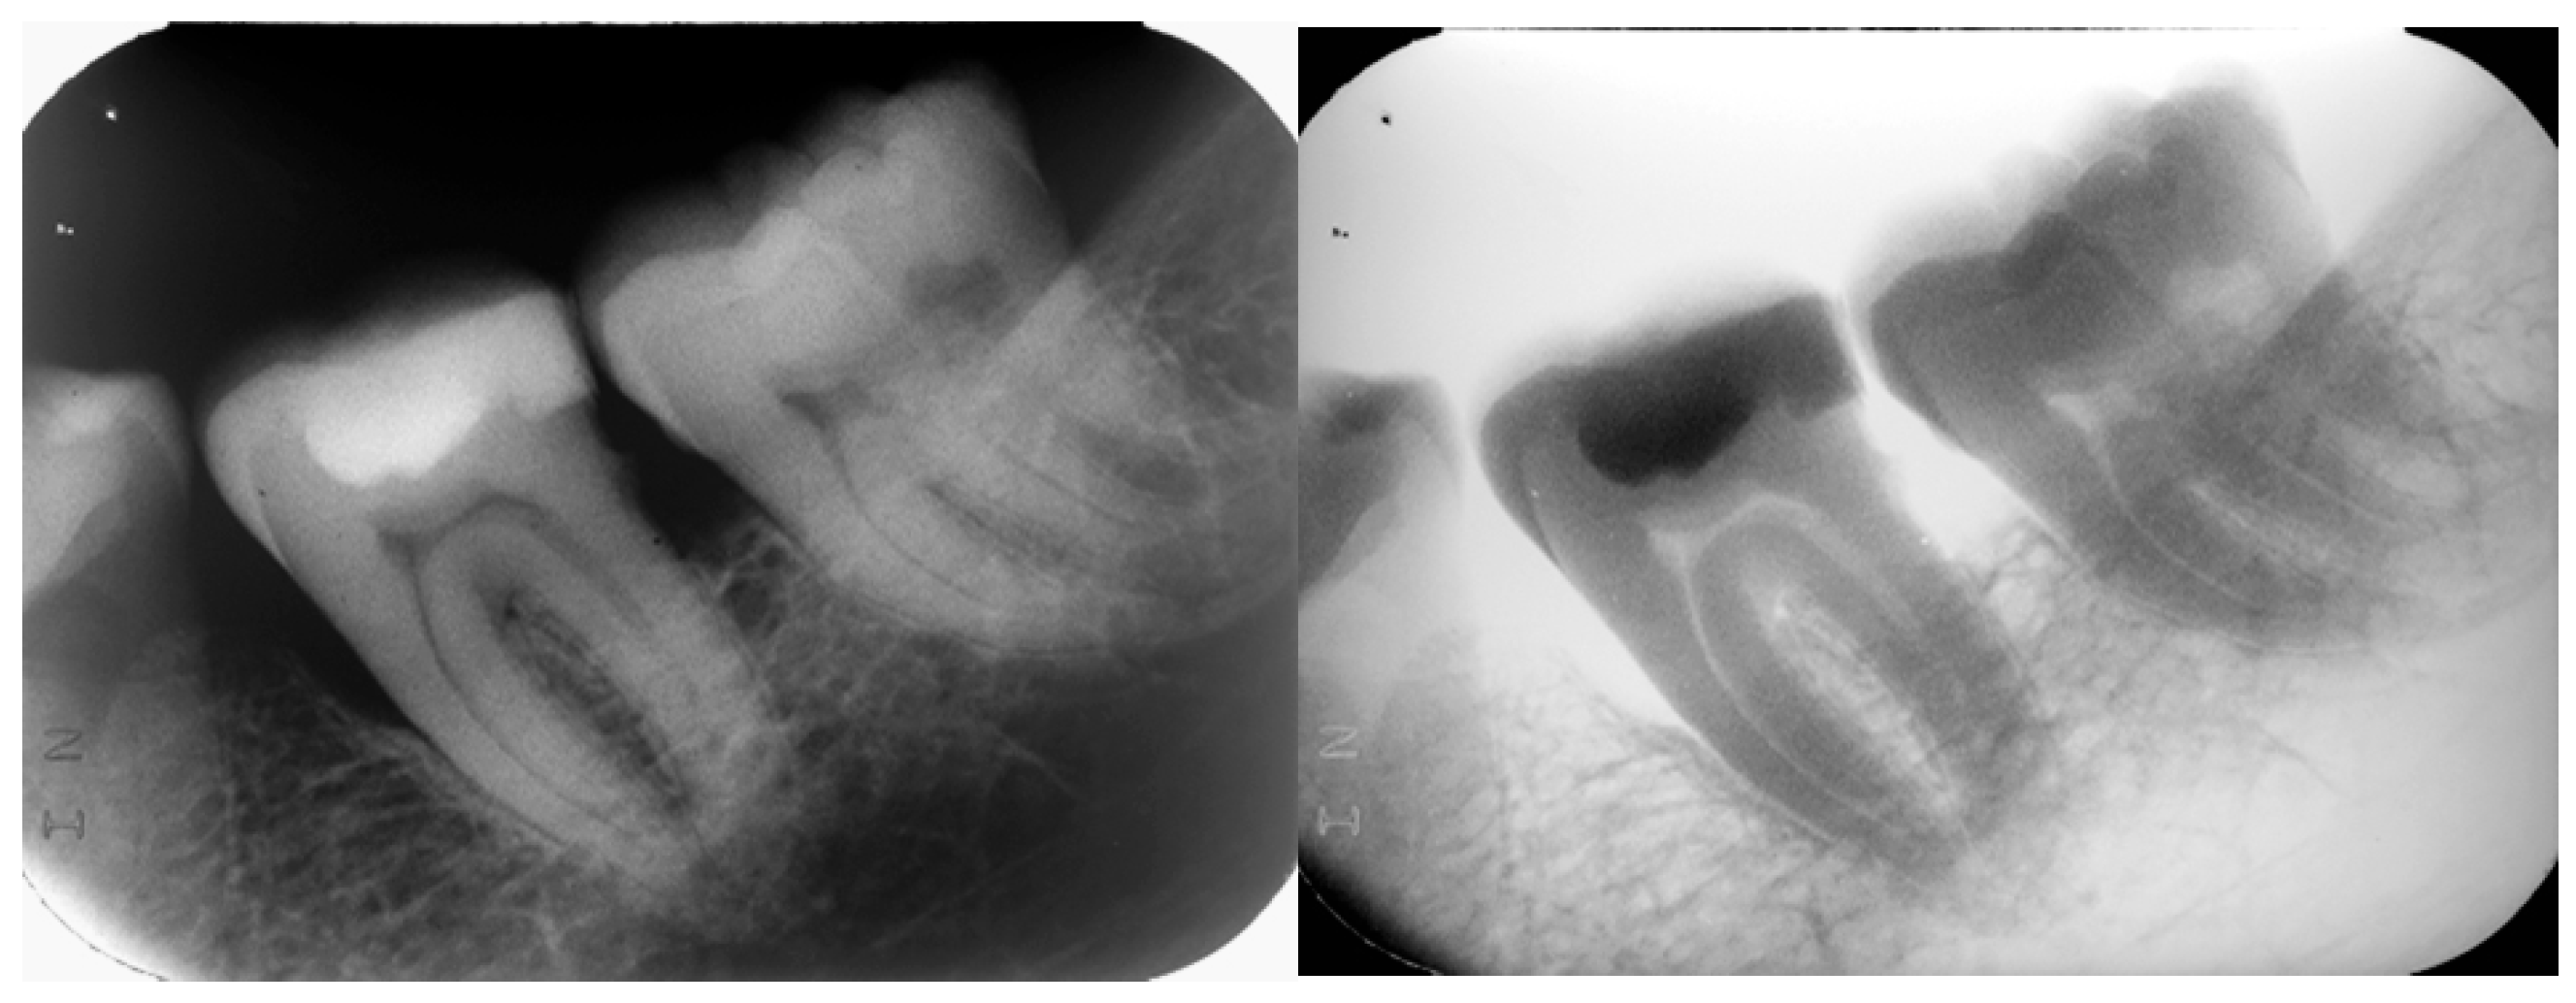

A 69-year-old Greek male patient presented in the dental office complaining about discomfort on the right maxillary area and asking for comprehensive oral treatment. During the clinical examination, a morphologically atypical molar was identified in the area of #37–38, presenting with a large crown in the mesio-distal dimension (‘double’ crown) (Figure 1). The patient reported having a panoramic radiograph taken two months ago, which revealed the internal structure of the deviating tooth, along with the neighboring teeth and bone structures. To develop the treatment plan, which included periodontal treatment, restorative procedures and fixed prosthetics, selected intraoral radiographs were additionally performed, as well as diagnostic casts (Figure 2).

Figure 1. Intraoral photograph, left mandibular posterior area.